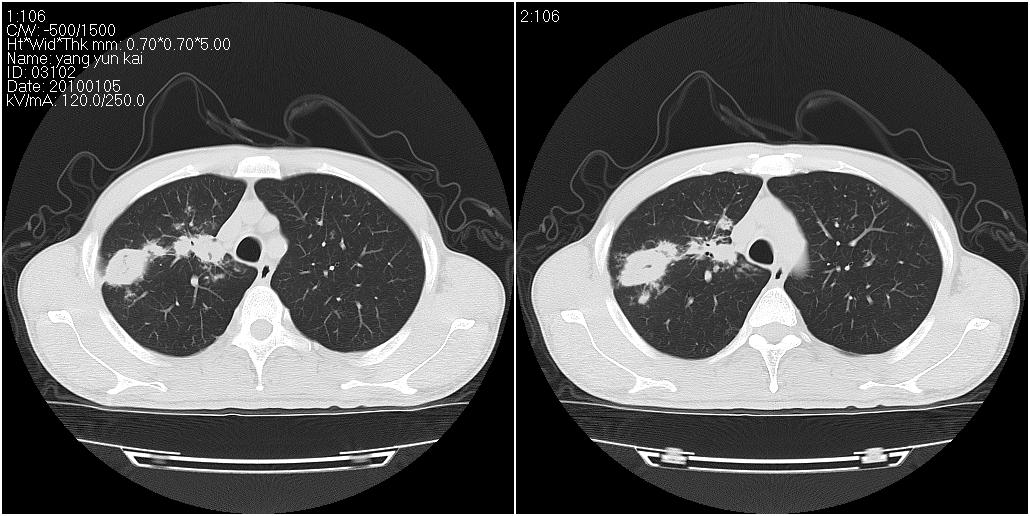

标题: CT23980:男性,47岁。近来咳痰、咳血,血沉增快(40左右),

男性,47岁。近来咳痰、咳血,血沉增快(40左右),痰中未检出结核杆菌。

两肺继发性肺结核并多发性结核球形成,部分病灶内空洞形成。

符合继发性结核表现部分空洞形成并播散